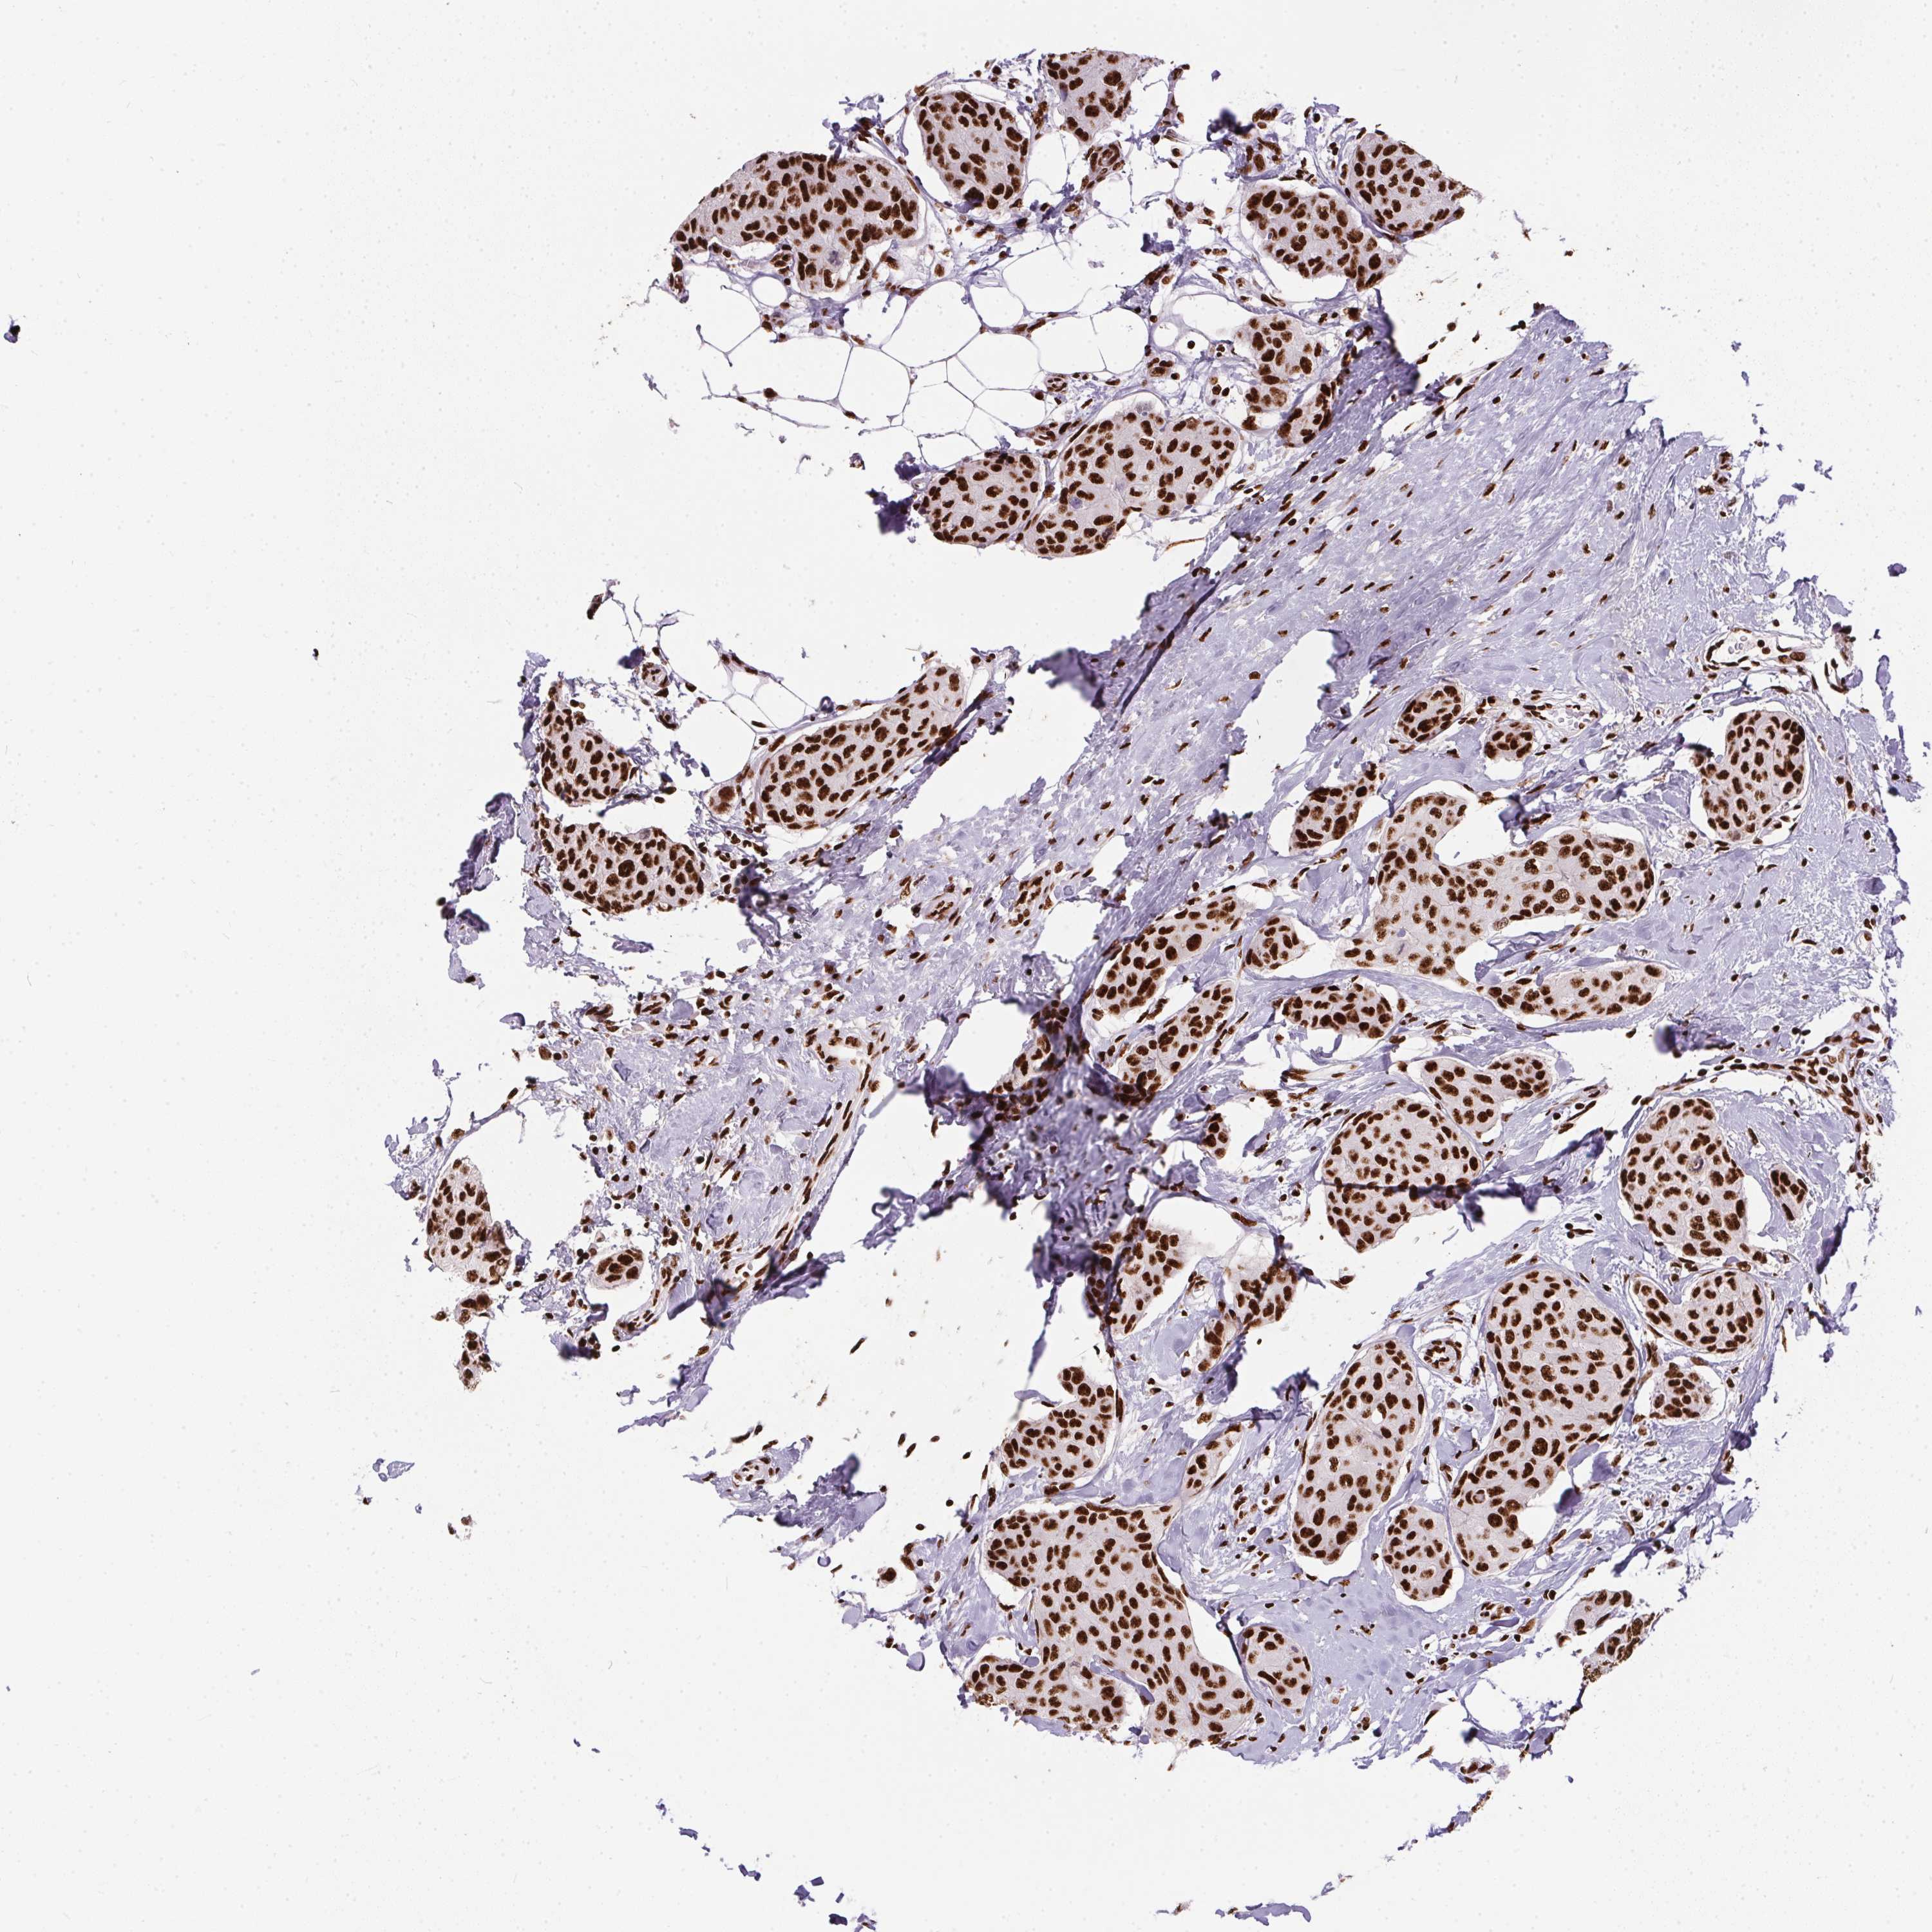

CANCER BREAST CANCER Show tissue menu

Breast cancer

Human cancer